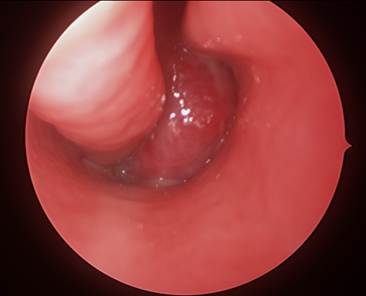

Identify the marked structure

Options:

- Thyroid cartilage

- Epiglottis

- Pyriform sinus

- Valllecula

Correct Answer: C) Pyriform sinus